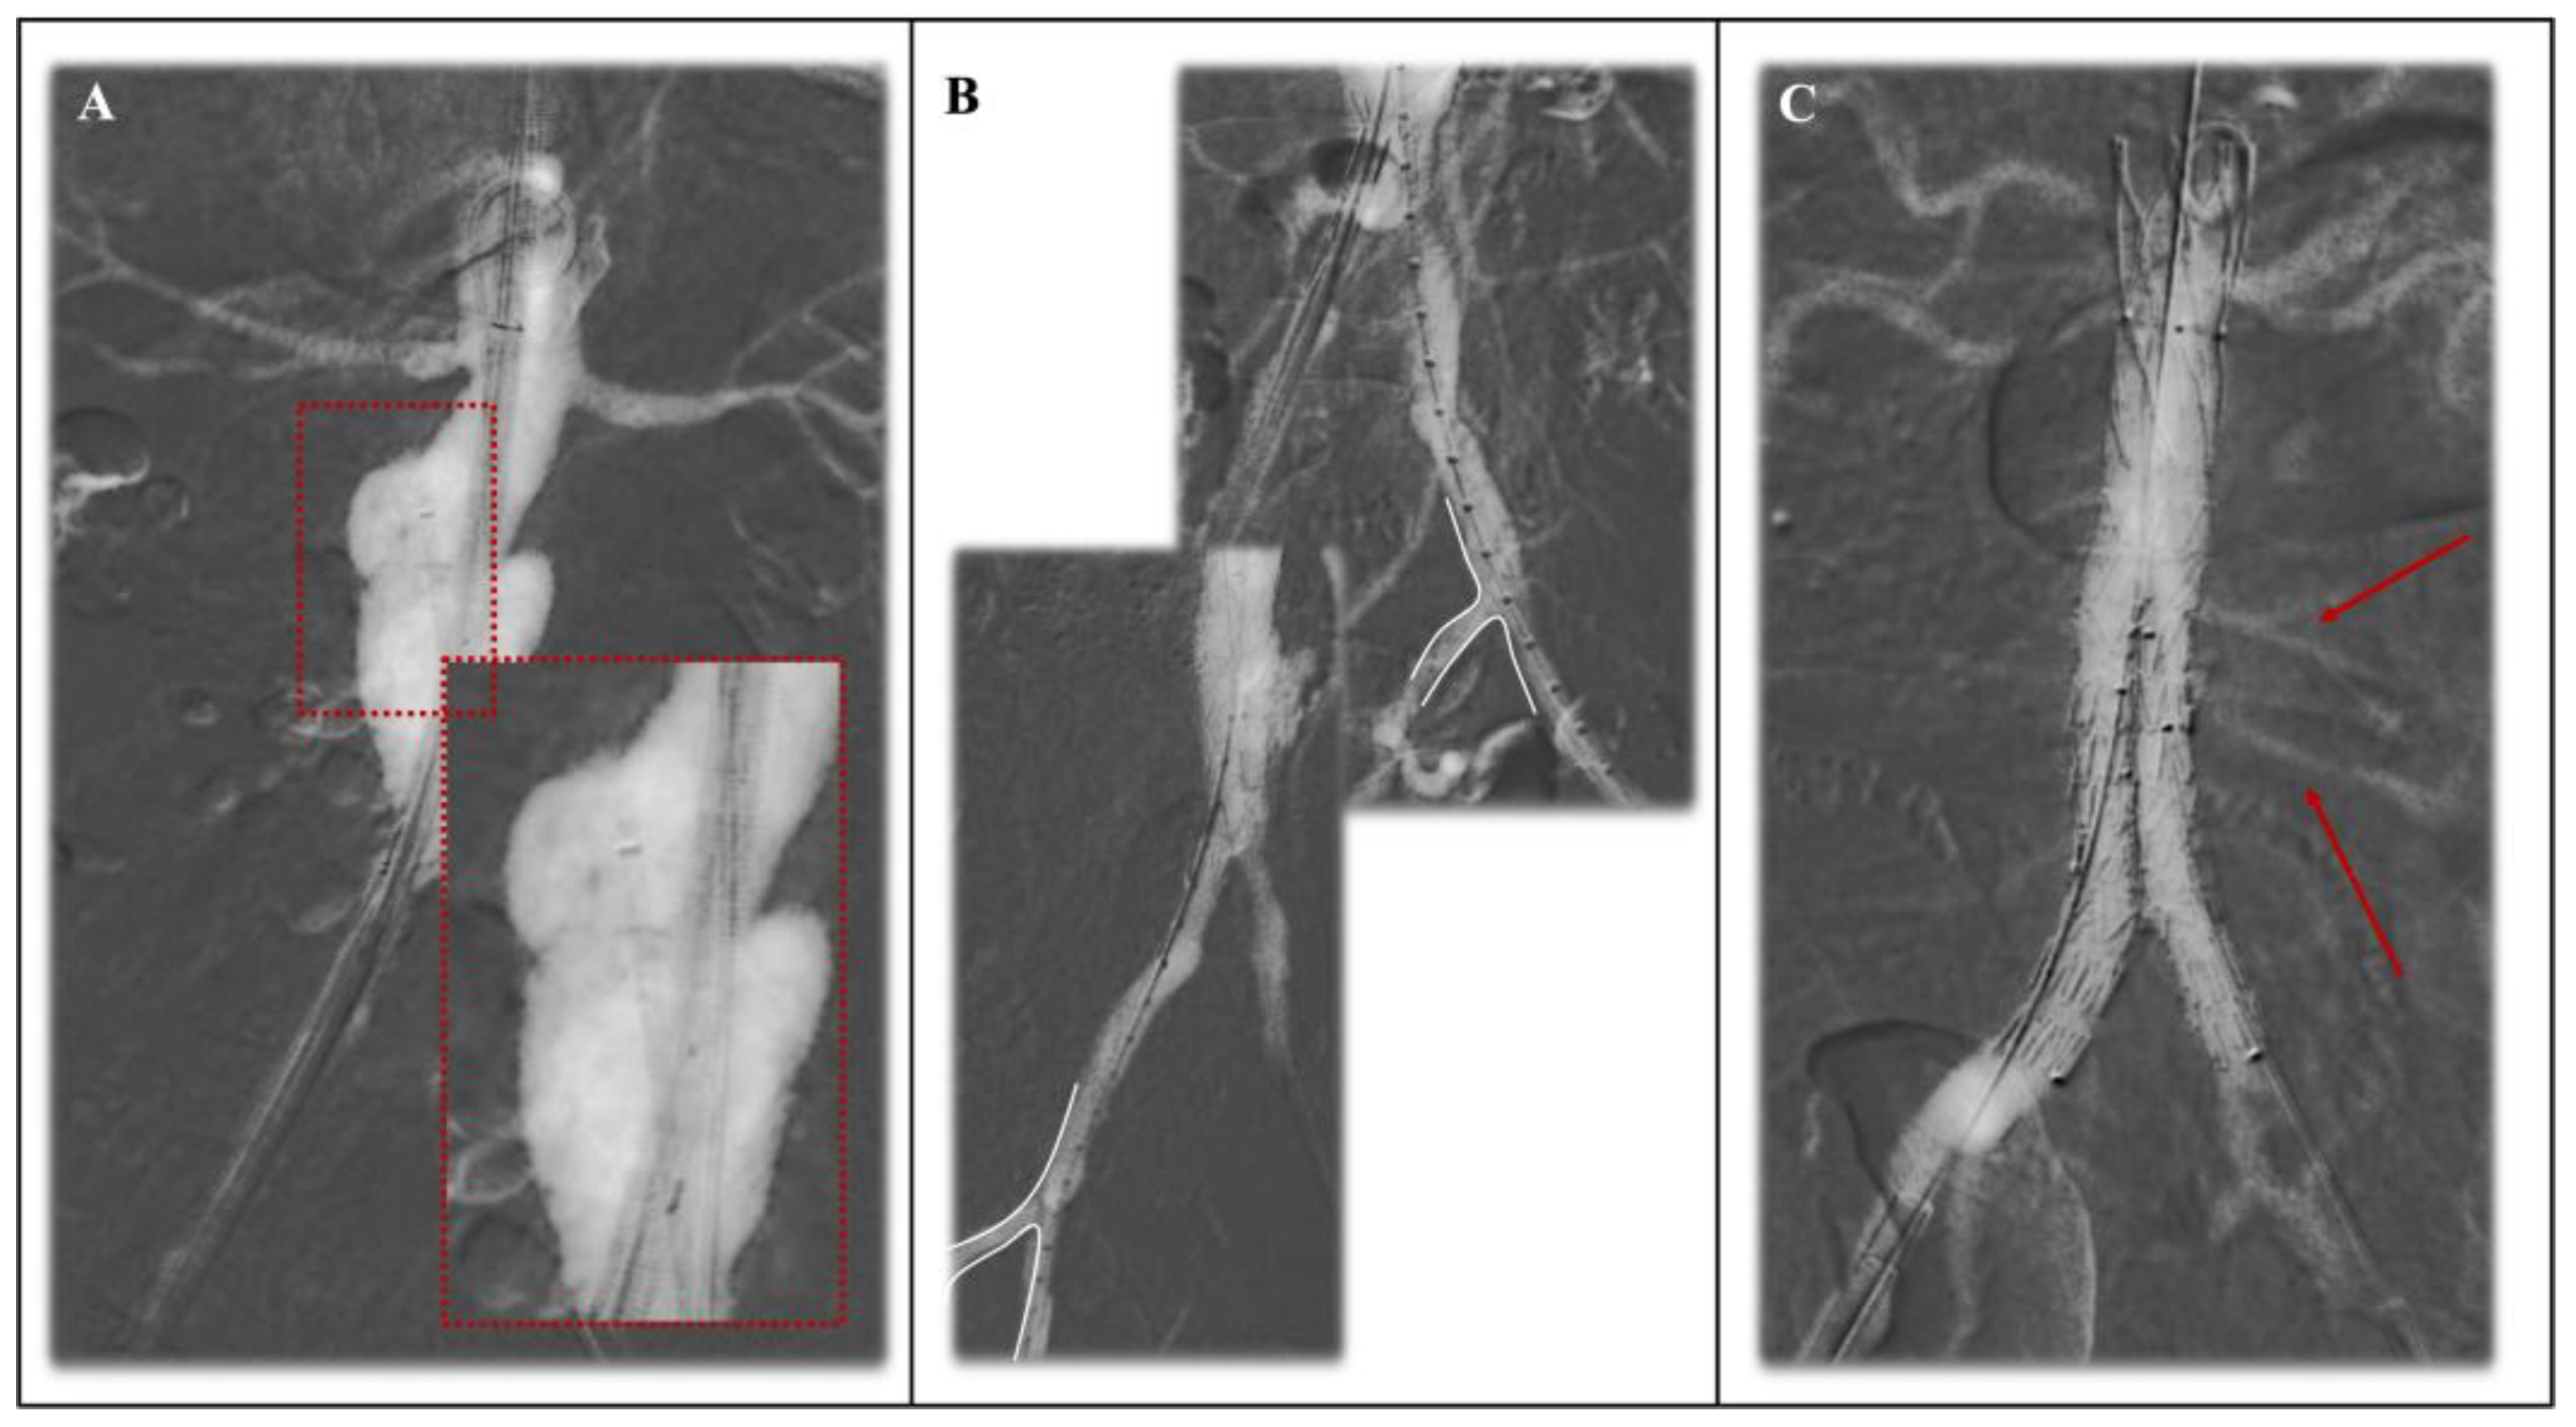

- Mascoli, C.; Faggioli, G.; Gallitto, E.; Vento, V.; Pini, R.; Vacirca, A.; Indelicato, G.; Gargiulo, M.; Stella, A. Standardization of a Carbon Dioxide Automated System for Endovascular Aortic Aneurysm Repair. Ann. Vasc. Surg. 2018, 51, 160–169. [Google Scholar] [CrossRef]

- Vacirca, A.; Faggioli, G.; Mascoli, C.; Gallitto, E.; Pini, R.; Spath, P.; Logiacco, A.; Palermo, S.; Gargiulo, M. CO2 Automated Angiography in Endovascular Aortic Repair Preserves Renal Function to a Greater Extent Compared with Iodinated Contrast Medium. Analysis of Technical and Anatomical Details. Ann. Vasc. Surg. 2022, 81, 79–88. [Google Scholar] [CrossRef]

- Vacirca, A.; Faggioli, G.; Vaccarino, R.; Dias, N.; Austermann, M.; Usai, M.V.; Oberhuber, A.; Schäfers, J.F.; Bisdas, T.; Patelis, N.; et al. The Optimal Operative Protocol to Accomplish CO2-EVAR Resulting from a Prospective Interventional Multicenter Study. J. Vasc. Surg. 2023, 77, 1405–1412.e1. [Google Scholar] [CrossRef]